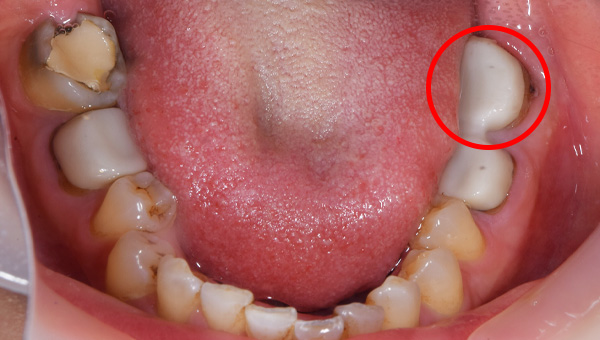

移植する歯

説明:

骨のスペースを確保したら移植する歯を抜きます。

移植した歯

移植した歯のレントゲン写真

移植した歯の写真です。隣の歯とワイヤーで固定します。約3週間でワイヤーは外します。